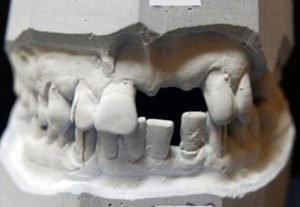

Prosthetic treatment in a toothless jawbone carried - 4 implants

Implantation solution of the posterior toothless sections in the jaw

Solution of frontal defect in the jaw

Solution of frontal defect in the jaw in a jaw orthopedic anomaly